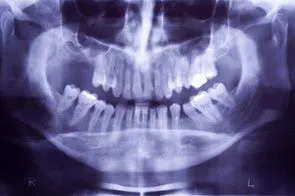

Loss of posterior teeth may result in excessive forces being placed on your remaining teeth.  Fortunately, the use of dental implants and crowns allow you to replace these missing teeth.  However, the position of the sinus in the upper posterior areas may be too low for proper placement of dental implants.

A simple procedure allows the sinus floor to be repositioned, creating enough space to properly place an implant.  Various grafting materials are used to encourage your bone to grow more quickly into the area, helping to stabilize the dental implant. Replace with your own bone in this area the grafting material as it grows into the area.

Under certain conditions, an even simpler procedure can be utilized.  When possible, the bone remaining under the sinus floor is gently “pushed up”, thus lifting the floor of the “dropped” sinus.  Bone replacement materials are then placed beneath this lifted bone.  Once again the bone materials are replaced as your body grow new bone into this area.

Sinus augmentation procedures are highly predictable, with studies reporting over 95% success.  Following sufficient healing of a sinus augmentation (6-10 months), implants are placed in a predictable and successful manner.  It is important to realize that if the sinus augmentation procedure does not result in enough bone for implant placement, additional bone may be regenerated through a second sinus augmentation procedure at the time of implant placement.